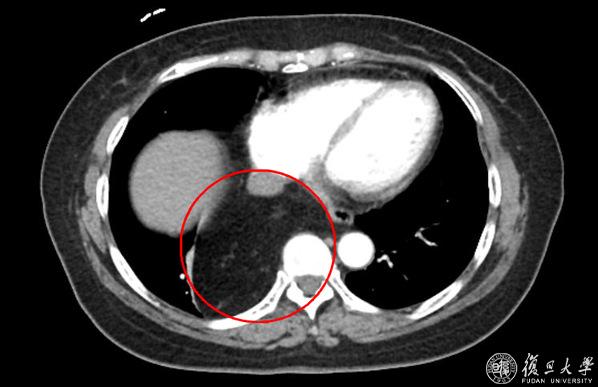

当地医院CT报告显示:右后下纵隔脂肪来源肿瘤。肿瘤进入腹腔、与周围组织分界不清。

一家人被吓的不轻,开始辗转求医。然而经过多次会诊研讨,当地医院认为欧阳女士的病情复杂,无法处理。经过多方打听,欧阳女士来到复旦大学附属中山医院普外科-腹膜后及软组织肿瘤外科主任张勇主任医师处就诊。在仔细询问了病史并查看CT影像后,张医生发现欧阳女士的“肿瘤”位于后纵膈,且密度均匀,考虑是脂肪组织。可是,这么多的脂肪从哪里来的呢?难道真的是罕见的脂肪肉瘤?

张医生随即安排欧阳女士复查增强CT,并请腹膜后及软组织肿瘤外科疝与腹壁外科专业组的杨子昂副主任医师,胸外科蒋伟副主任医师一同会诊。在放射科的协助下,多位专家仔细研究了欧阳女士的影像学表现,考虑她的“肿瘤”是疝入“食管裂孔疝”内的脂肪组织,并不是真正的“肿瘤”。

经过周密的术前准备,在张勇主任医师的指导下,杨子昂副主任医师、蒋伟副主任医师、庄秋林主治医师为病人实施了腹腔镜手术。术中明确,欧阳女士胸腔内的肿块就是经食管裂孔疝入胸腔后纵膈内的大网膜!多学科手术团队逐步回纳疝内容物,仔细游离疝囊,关闭缺损。为了防止欧阳女士出现胃食管返流,又进一步完成了胃底折叠等手术步骤。经过1个多小时,最终完成食管裂孔疝修补+DOR胃底折叠术。